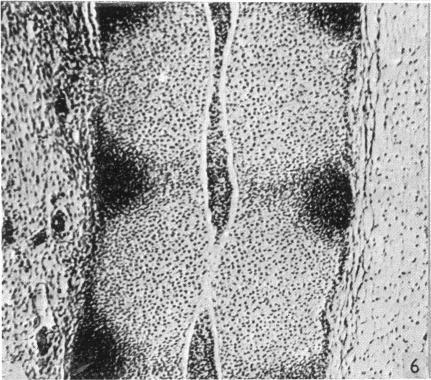

Observations on the prenatal development of the intervertebral disc in man.

J Anat. 1951 Jul;85(3):260-74.